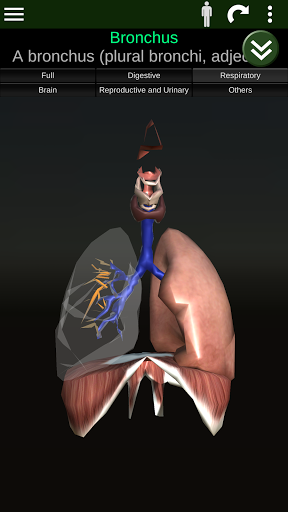

Menampilkan model anatomi 3D dari organ utama tubuh manusia dan penjelasannya masing-masing.

* Sistem pernafasan, yang meliputi trakea, bronkus, paru-paru dan animasi sistem ini.

* Mudah diakses dan dinavigasi (zoom, rotasi 3D).

* Deskripsi masing-masing organ.